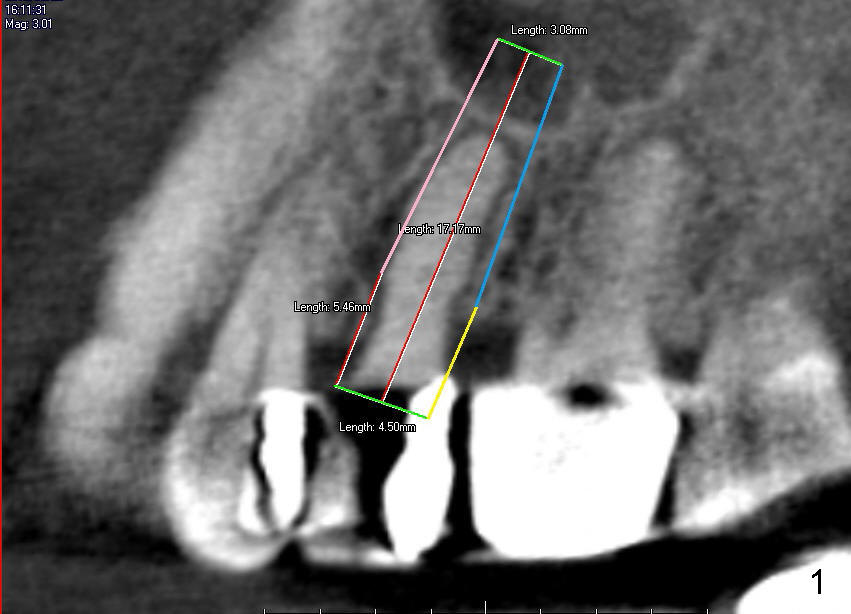

The tooth #13 has broken down to residual root now.  CBCT sagittal (Fig.1,3) and coronal (Fig.2,4) sections show designs of T (4.5x17 mm Fig.1,2) and D2 (Fig.3,4) implants.  Which is better?  It appears that sinus lift with bone graft is expected.